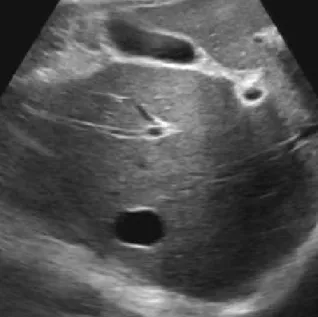

肝脓肿

● 定义:肝脓肿是肝脏的化脓性炎症,可由细菌、真菌或阿米巴原虫等感染引起。病理过程通常包括炎症浸润期、脓肿形成期和脓肿吸收期。

● 超声表现:

1.肝内单个或多个占位性病变。

2.早期呈低回声,边界不清,血流丰富。

3.脓液形成后,呈液性暗区,壁厚薄不均,内壁不平整,内透声差,可见絮状回声,有些可见分层。

4.肝脓肿进一步发展,内透声好,如肝囊肿,但壁厚薄不均。

5.后方结构(后壁)回声增强。